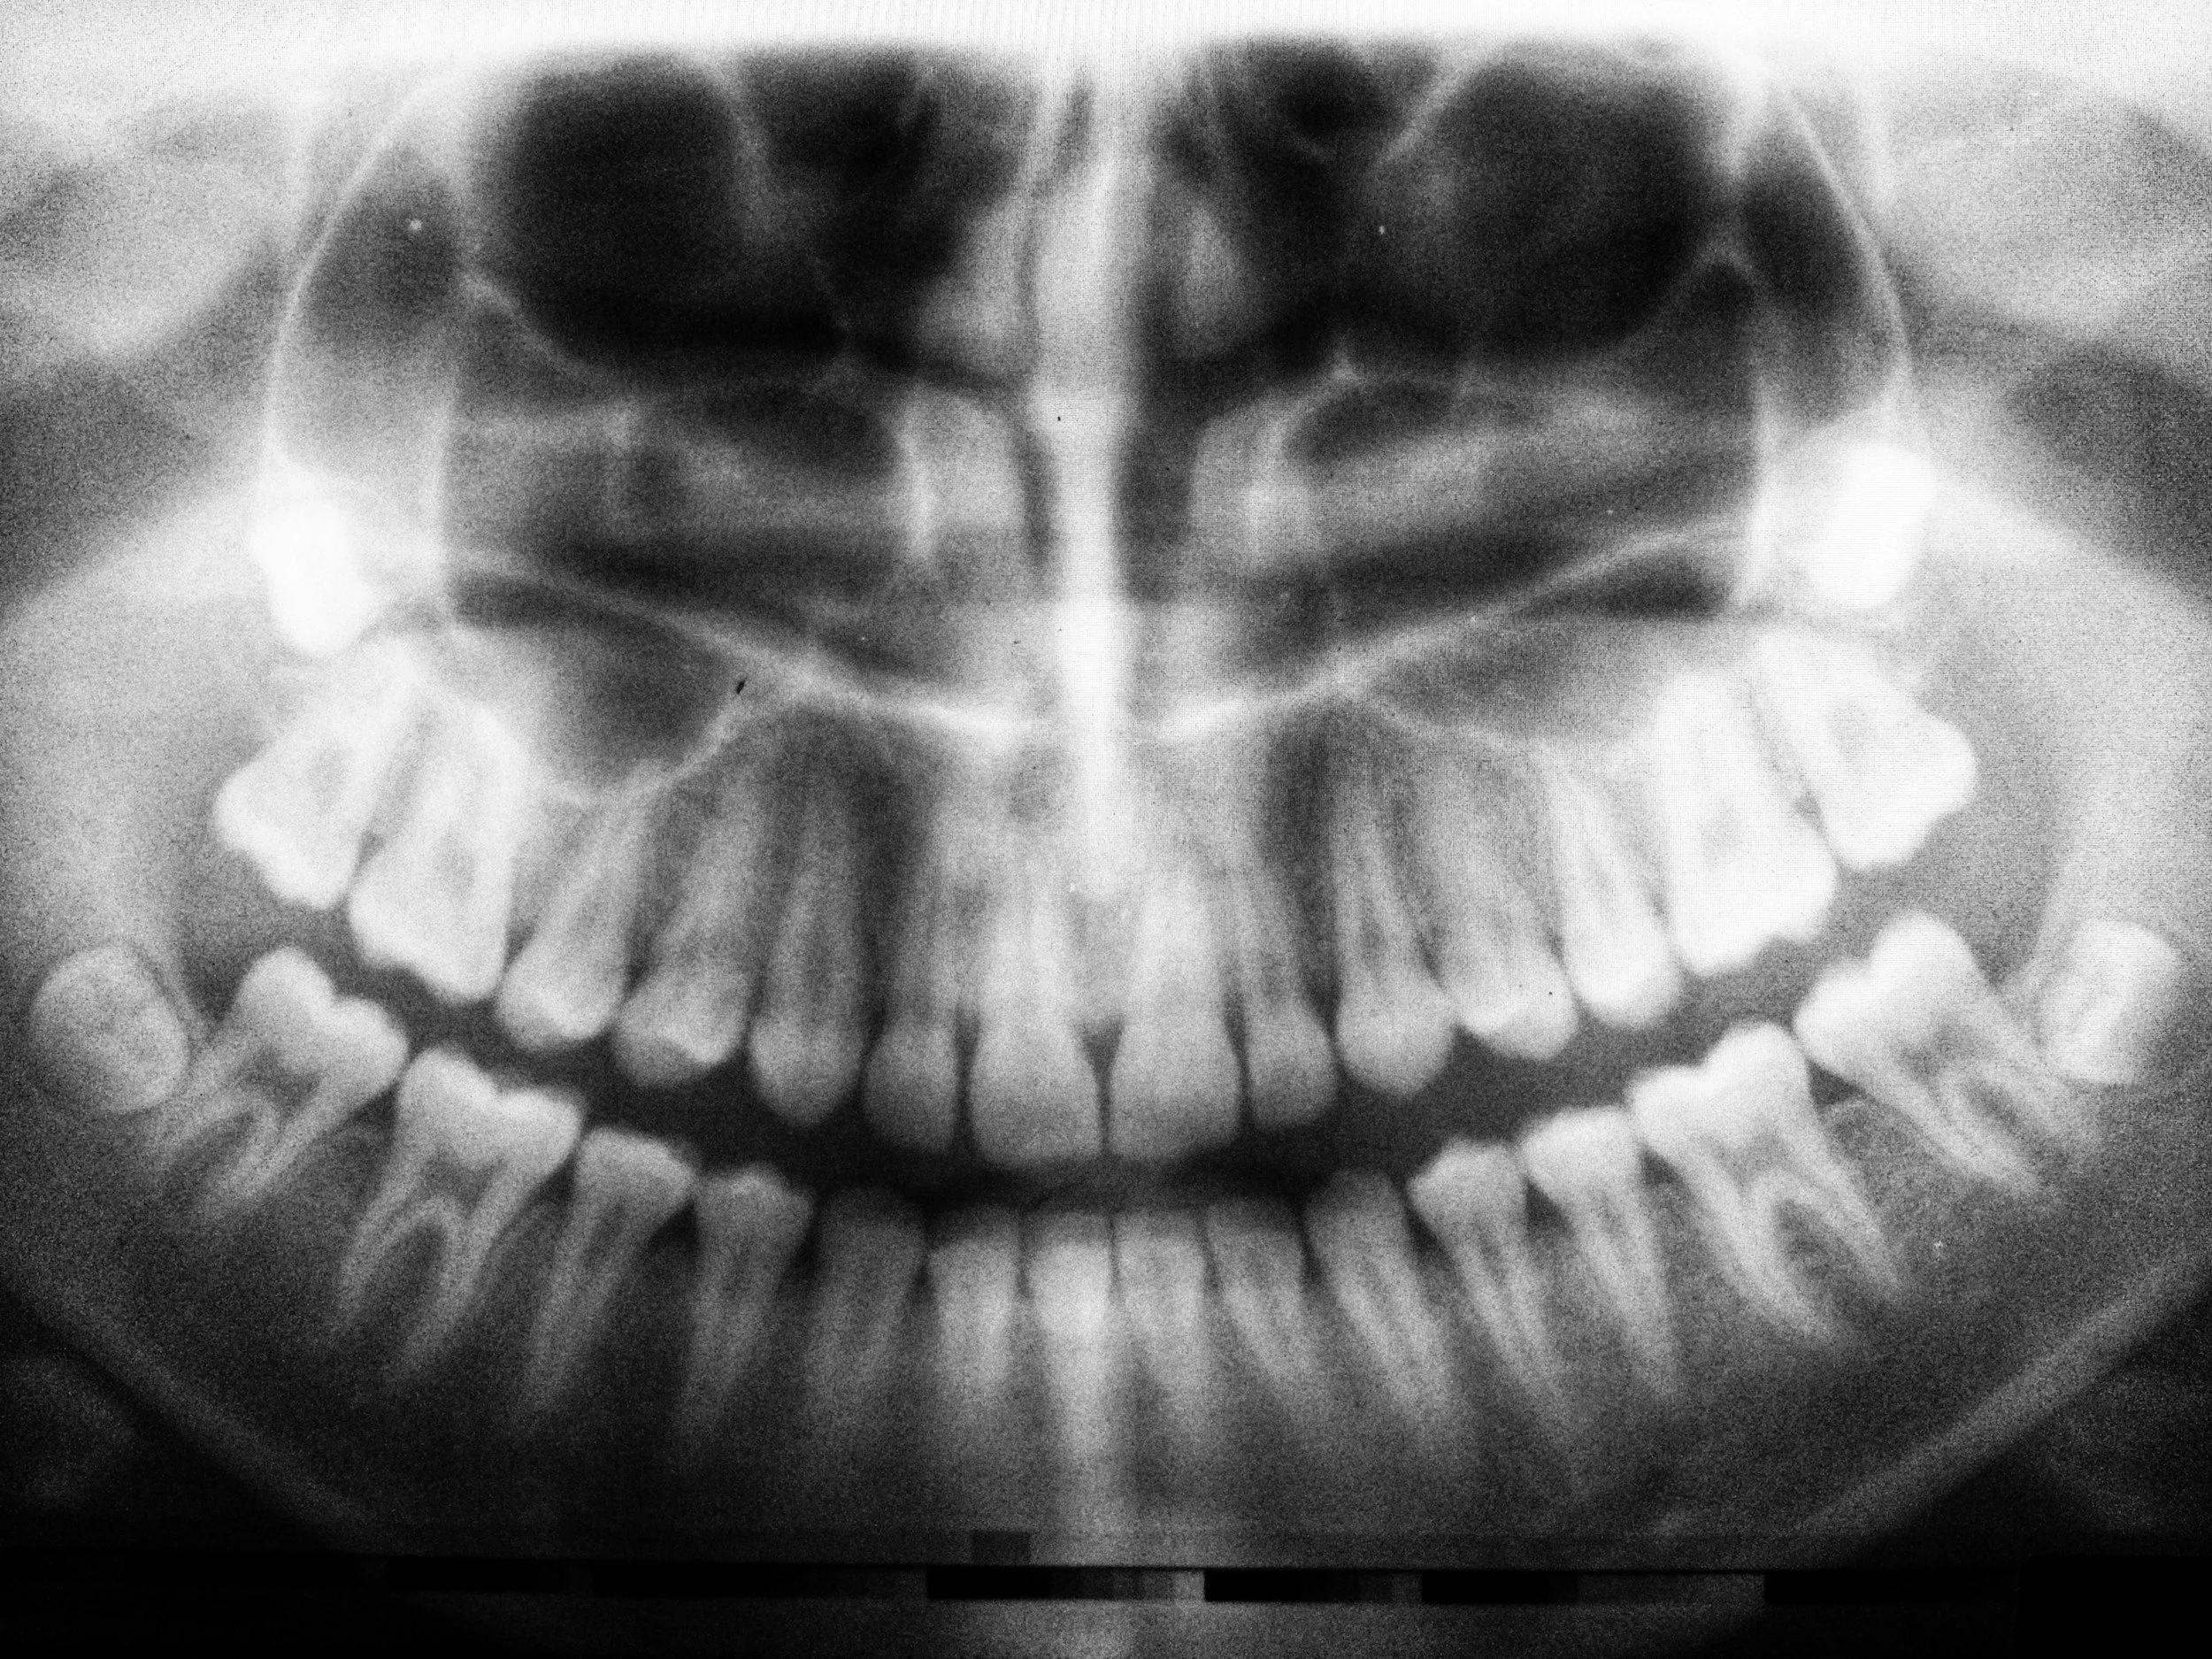

• Comprehensive oral examinations

• Early detection of cavities or gum disease

• Evaluation of bite and existing dental work